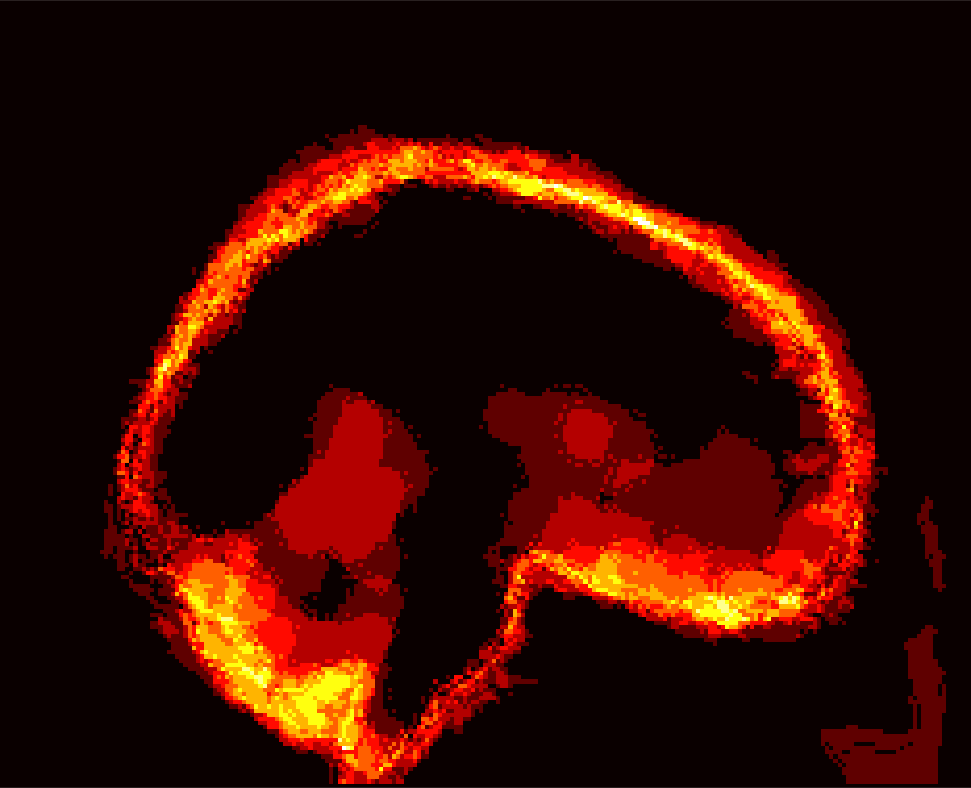

[Uncaptioned image] [Uncaptioned image] [Uncaptioned image] [Uncaptioned image]

(a) (b) (c) (d)

Figure 8: Example BRATS image with its decomposition result in atlas space. (a) Input image after pre-processing; (b) quasi-normal image L+M𝐿𝑀L+M; (c) non-brain image S𝑆S; (d) pathology image T𝑇T.

In addition to extracting the brain from pathological datasets, our method also allows for the estimation of a corresponding quasi-normal image in atlas space, although this is not the main goal of this paper. Fig.8 shows an example of the reconstructed quasi-normal image (L𝐿L) for an image of the BRATS dataset, as well as an estimation of the pathology (pathology image T𝑇T and non-brain image S𝑆S). Compared to the original image, the pathology shown in the quasi-normal image has been greatly reduced. Hence this image can be used for the registration with a normal image or a normal atlas. This has been shown to improve registration accuracy for the registration of pathological images [27]. Furthermore, an estimate of the pathology (here a tumor) is also obtained which may be useful for further analysis. Note that in this example image the total variation term captures more than just the tumor. This may be due to inconsistencies in the image appearance between the normal images (obtained from OASIS data) and the test dataset. As our goal is atlas alignment rather than quasi-normal image reconstruction or pathology segmentation, such a decomposition is acceptable, although we could improve this by tuning the parameters or applying regularization steps as in [27].